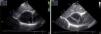

Echocardiography (Figure 3) was repeated and revealed an echo-free structure containing a septum, pushing on the right atrium and visualized only from subcostal view, which showed a large pericardial cyst, and no other abnormal findings.